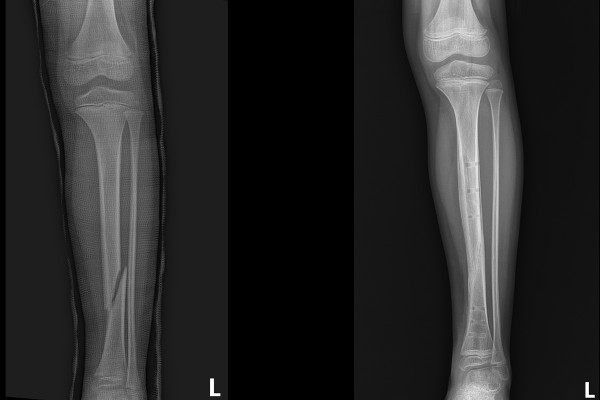

수술 후 X-RAY를 보면 강하게 고정되어 어긋남 없이 올바르게 정렬된 것이 확인됩니다.

수술 후 약 2주 정도는 목발 사용과 함께 반깁스를 착용하고, 3주차부터는 목발 없이 발을 다 디디게 됩니다. 5~6주가 지난 시점에서는 뛰어다니며 학교에서 체육활동도 다 하면서 지내시다가 수술 후 약 3개월이 지난 시점에서 삽입물을 제거하게 됩니다.